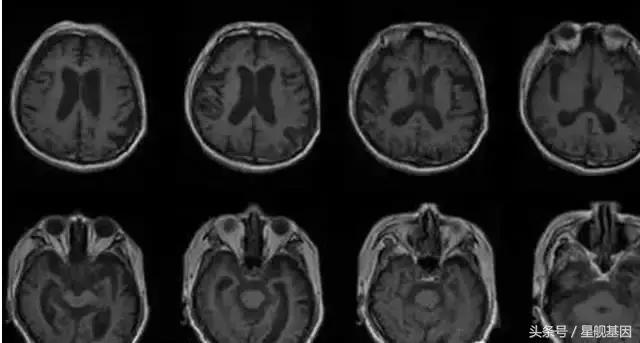

脑胶质瘤,又称神经胶质瘤,其中以星形细胞瘤和极性成胶质细胞瘤较为多见,其次是少枝胶质细胞瘤、室管膜胶质瘤、髓母细胞瘤,此外还可见到血管瘤、囊肿、畸胎瘤、结核瘤、转移性肿瘤等。

脑胶质瘤在发生之初,通常没有典型的症状。随着肿瘤的不断增大,会表现出如下症状:一是颅内压增高和其他一般症状,如头痛、呕吐、视力减退、复视、癫痫发作和精神症状等。另一是脑组织受肿瘤的压迫、浸润、破坏所产生的局部症状,局部症状依肿瘤生长位置不同而异。

脑胶质瘤这么凶险吗?的确,脑胶质瘤很凶险。胶质瘤系浸润性生长物,它和正常脑组织没有明显界限,难以完全切除,对放疗化疗不甚敏感,非常容易复发,生长在大脑等重要部位的良、恶性肿瘤,手术难以切除或根本不能手术。化学药物和一般抗肿瘤的中药,因血脑屏障等因素的影响,疗效也不理想,因此脑胶质瘤至今仍是全身肿瘤中预后最差的肿瘤之一。